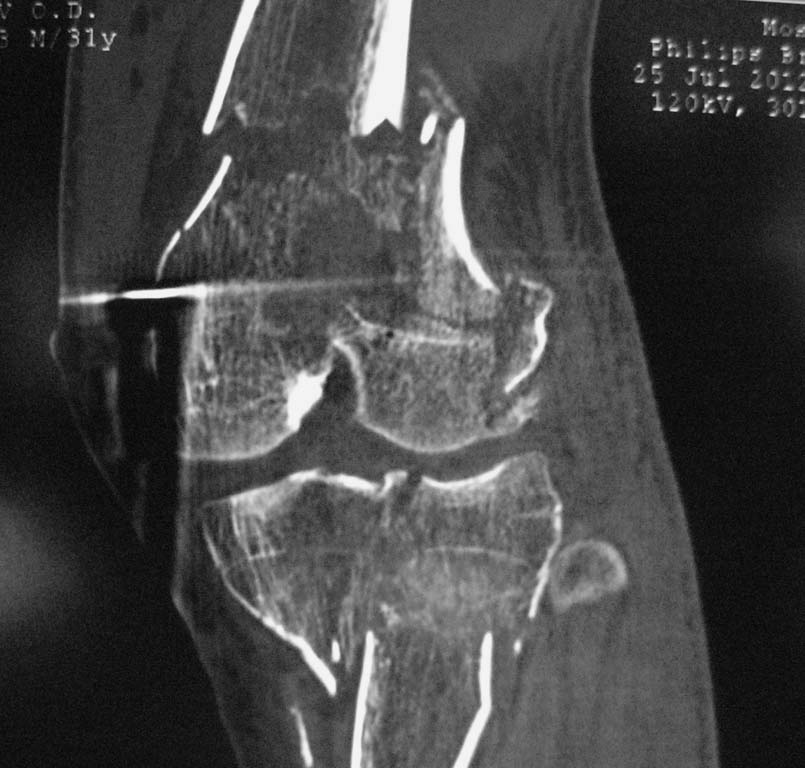

Нужен совет. Открытый перелом в\3 диафиза с оскольчатым переломом дистального метаэпифиза бедра. Закрытый оскольчатый внутрисуставной перелом проксимального отдела большеберцовой кости той же конечности.

При поступлении ПХО ран, скелетное вытяжение. Рана зажила первичным натяжением. Осложнилось правосторонней пневмонией. Предстоит выбрать тактику оперативного лечения и камими имплатнатами.